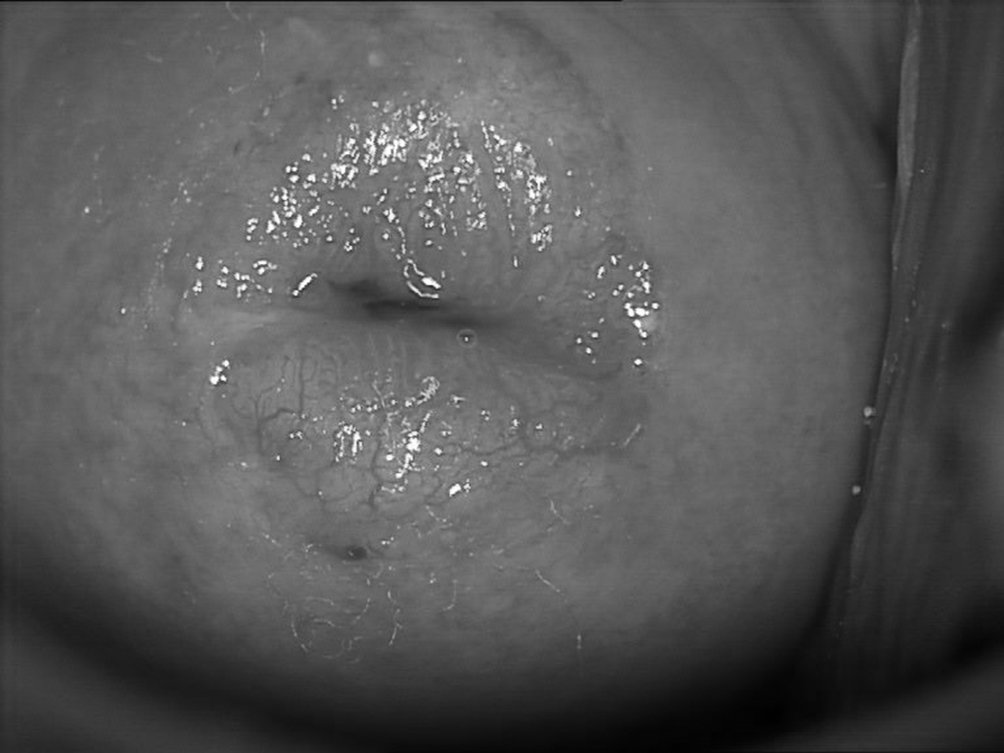

Figure 18.2 Ectropion : examen colposcopique sans préparation.